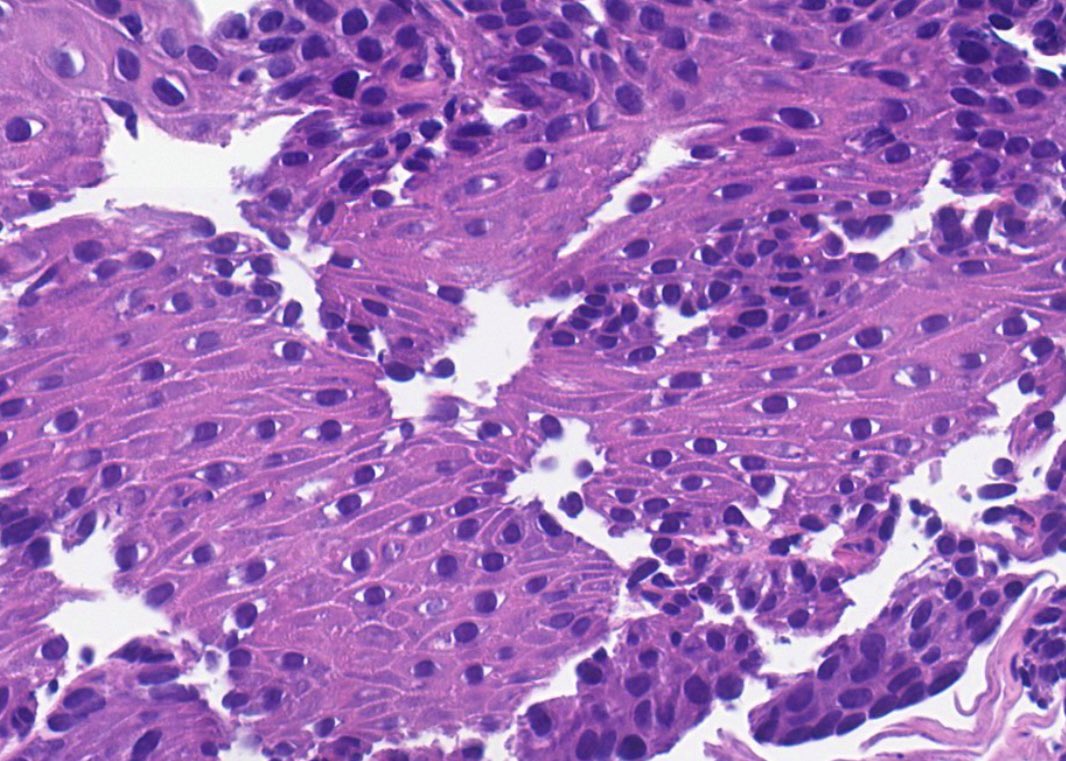

Merkel cell carcinoma: small metastasis in a lymph node. Very nice cellular contrast on H&E alone. Salt-and-pepper chromatin. #RealLifeDermpath #dermtwitter #dermpath